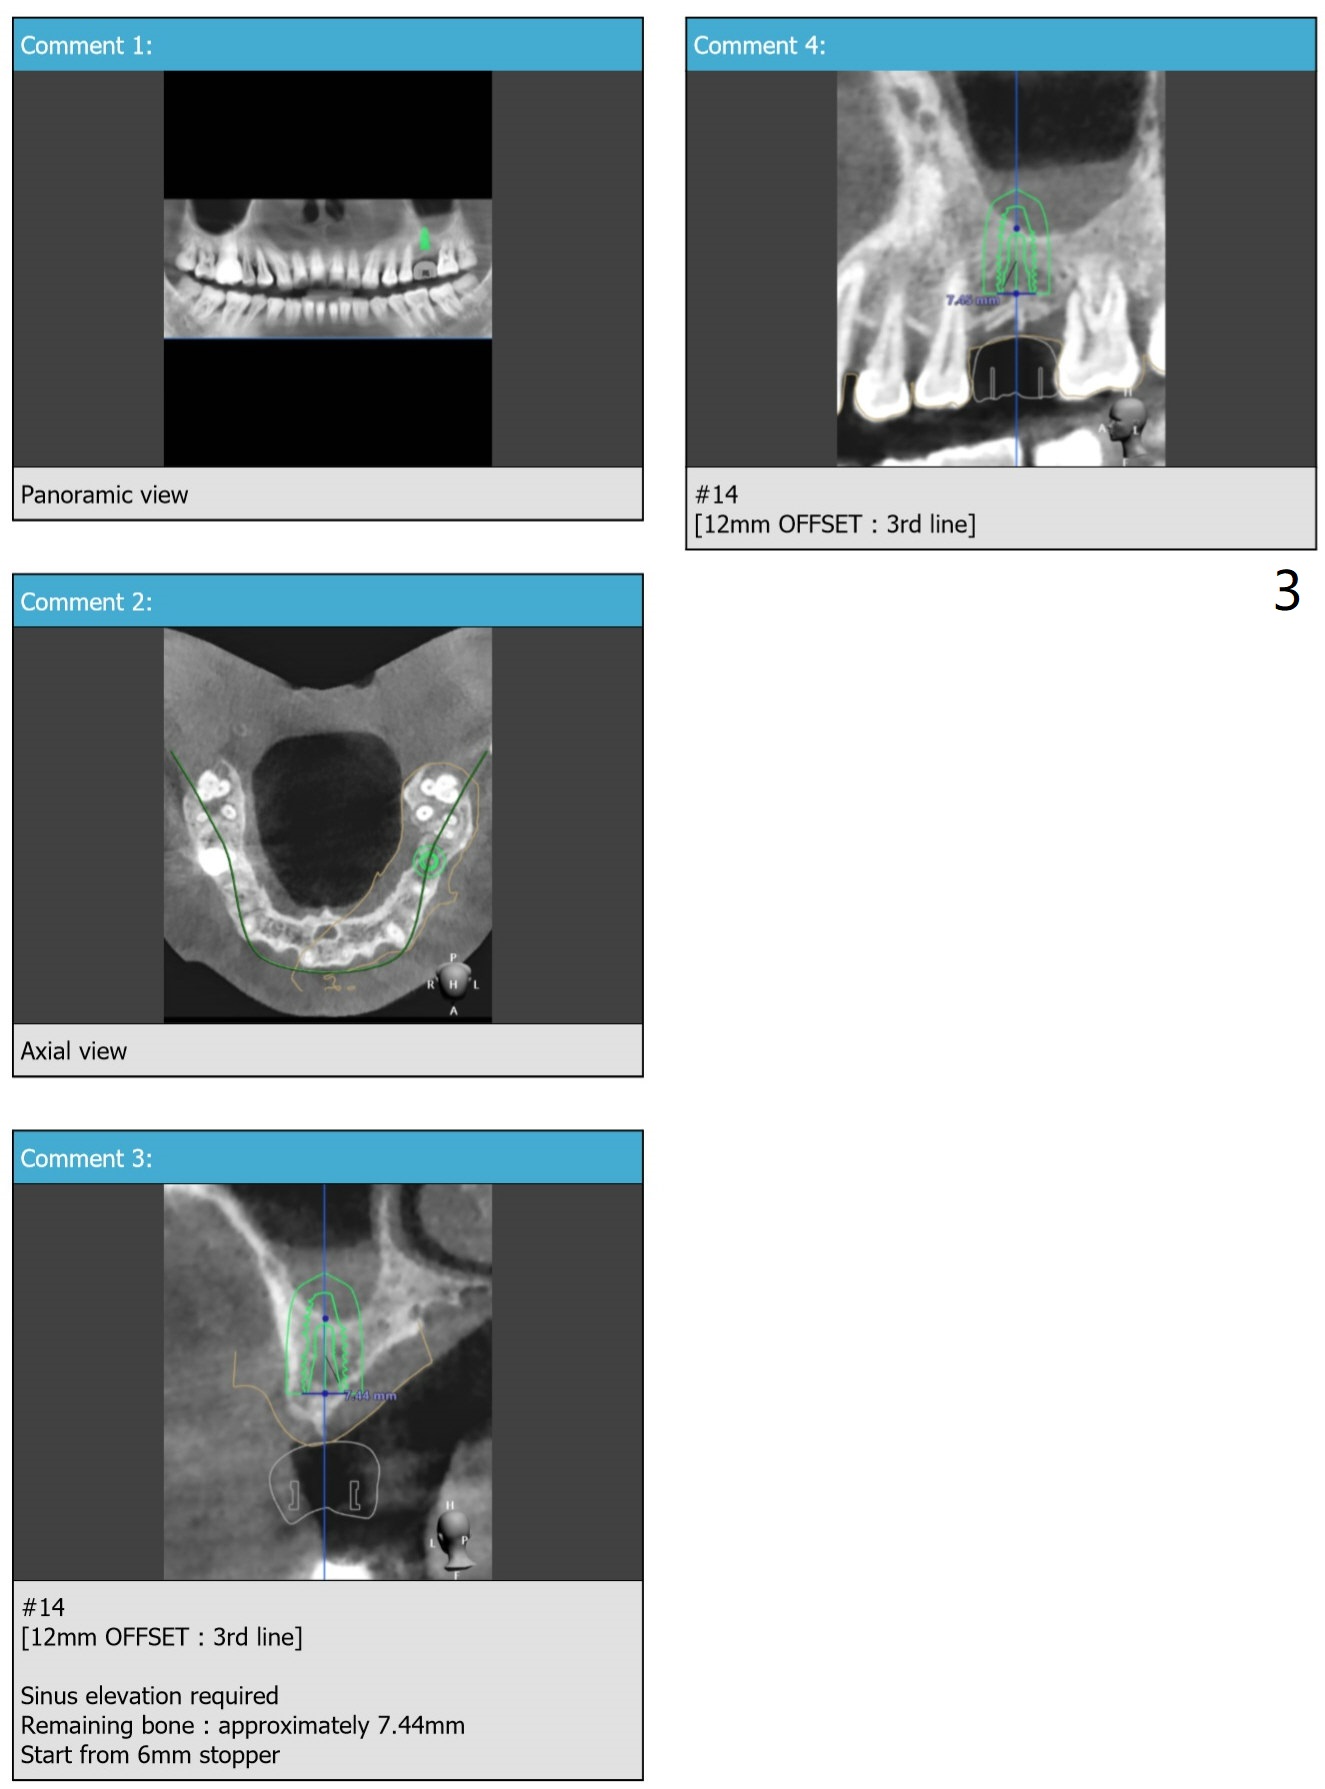

is to place an implant deep with sinus lift. Although the final implant is Tatum (4.5x14 mm), use IS 4 or 4.5x10 mm dummy implant to finish sinus lift. Also prepare BW for implant placement level. Trim the mesial bone if necessary. Or start osteotomy depth first, probably until 8.5 mm, increase the diameter and check the sinus floor each step.